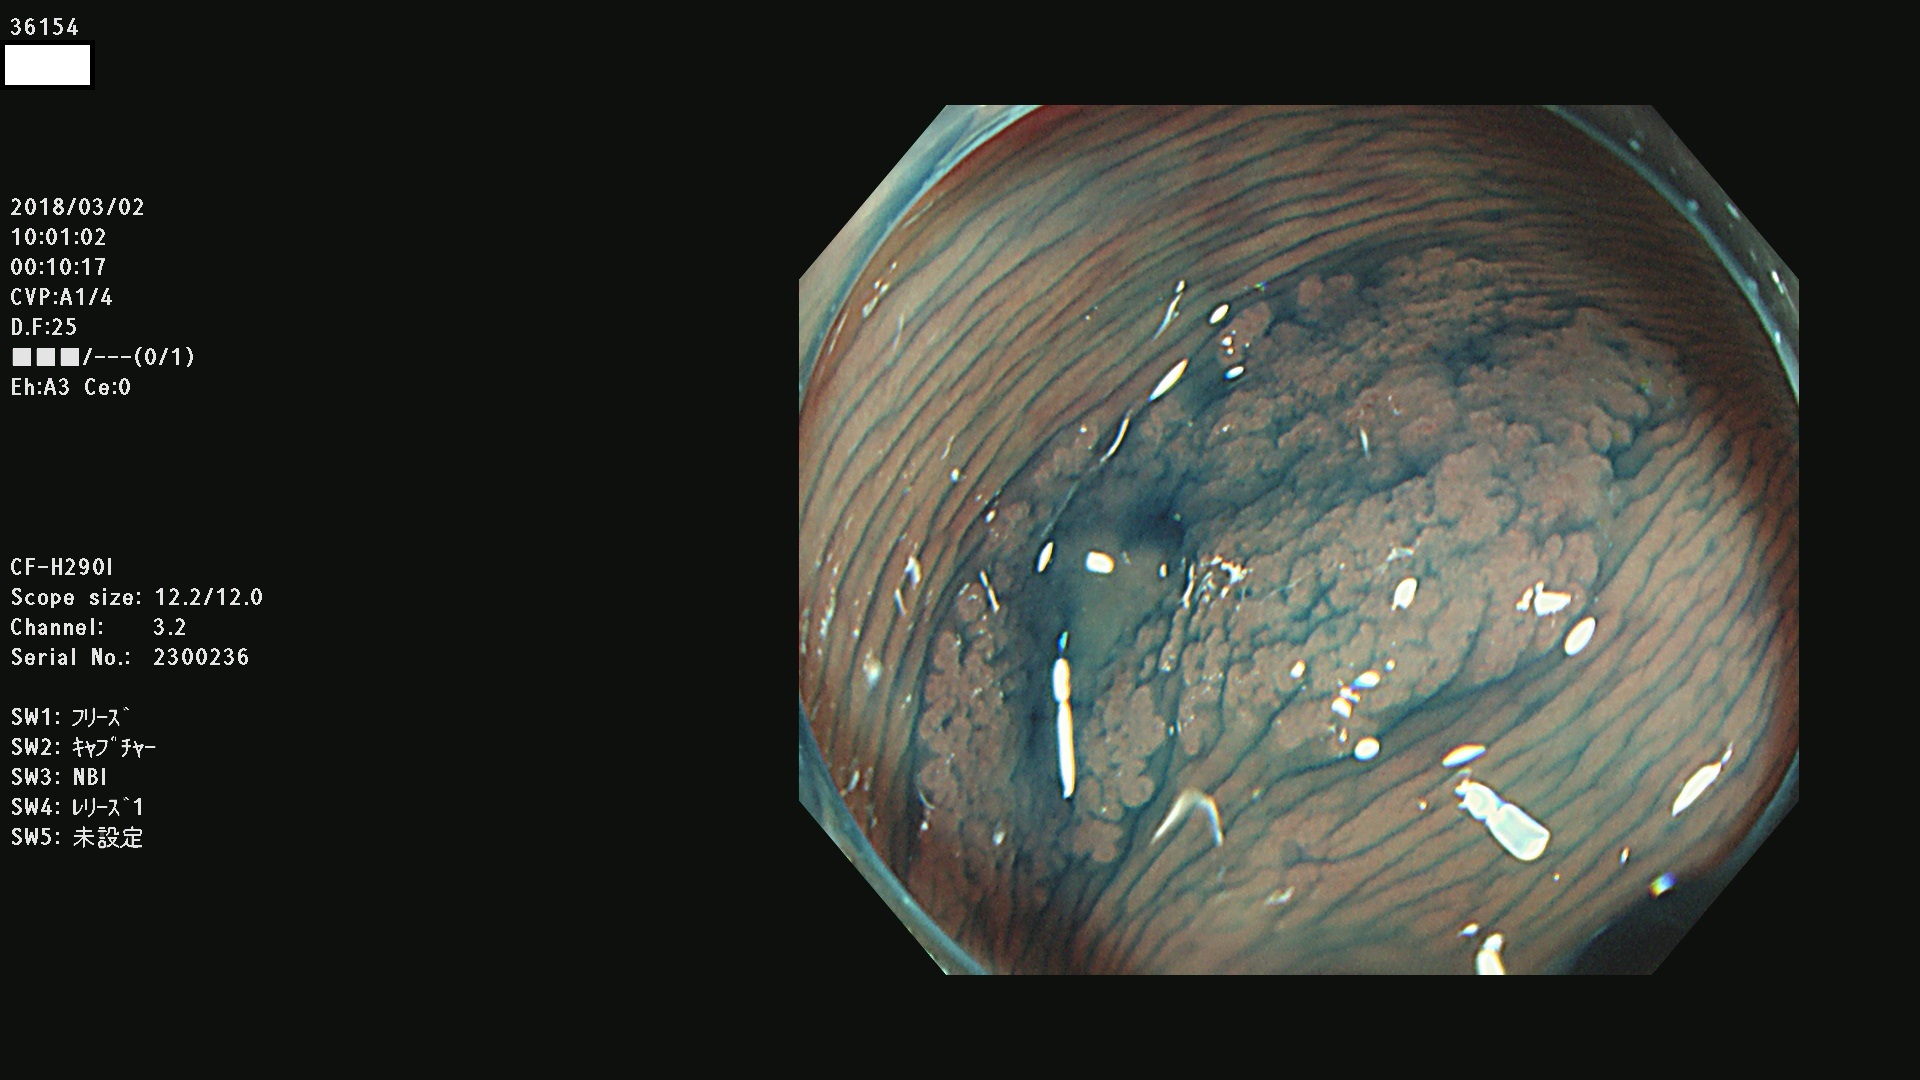

腺腫発見率57 % (カルテ番号 36100〜36199の100名の方の検査結果で集計)大腸癌検診最新情報

以下のカルテ番号の方に腺腫(Adenoma,Group3〜5)が見つかりました(集計法)

36100 36101 36102 36103 36104 36105 36107 36108 36110 36111 36114 36115 36117 36119 36120 36122 36125 36127 36129(SSA/Pのみ) 36133 36135 36137 36138 36139 36143 36144 36146 36147 36152 36153 36154 36155 36157(SSA/Pのみ) 36158 36162 36163 36165 36167 36169 36170 36173 36174 36176 36177 36178 36179 36180 36183 36185 36187 36189 36190(SSA/Pのみ) 36191 36193 36195(SSA/Pのみ) 36197(SSA/Pのみ) 36199(SSA/Pのみ)

発見困難で危険性の高い平坦型病変(上記100名より抽出) ![]()